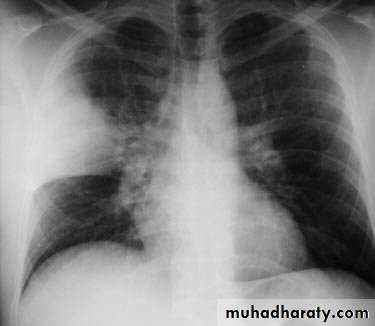

Lobar pneumonia: homogenous consolidation of one or more lung lobes, often with associated pleural effusion

A chest X-ray is usually sufficient to confirm the clinical diagnosis of pneumonia.

In lobar pneumonia, a homogenous opacity localized to the affected lobe or segment usually appears within 12 – 18 hours of the onset of illness.

Chest X-ray helps in:• Differentiating CAP from other diagnosis

• Provide information about severity (cavitation and multilobar involvement)

• Detects complications (pleural effusion or abscess formation).

• It can occasionally suggest an aetiological agent (pneumatocoele in Staphylococcus aureus pneumonia).